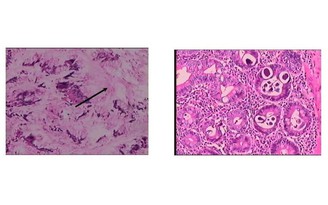

Với hệ thống thiết bị hiện đại như MRI 1.5 Tesla, MSCT 128 lát cắt và việc chính thức thông tuyến bảo hiểm y tế từ tháng 8.2025, người dân Long An nói riêng và Tây Ninh nói chung giờ đây có thể tiếp cận dịch vụ y tế kỹ thuật cao với chi phí hợp lý ngay tại Bệnh viện đa khoa quốc tế Tân An.